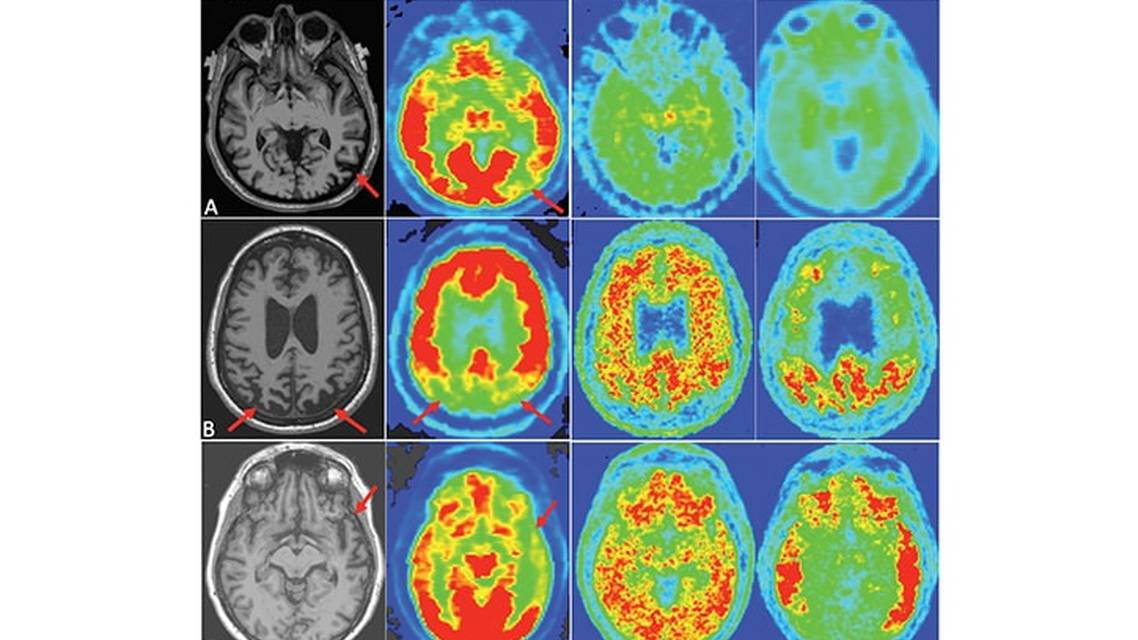

Next, Drs. Dickerson and Atri get to the heart of the matter in Molecular Imaging Biomarkers in Dementia, covering amyloid and tau positron emission tomography (PET). These PET scans specifically look for the proteins that malfunction in Alzheimer disease (AD) and related dementias. Amyloid imaging was approved by the Food and Drug Administration (FDA) in 2013, and tau imaging was FDA-approved earlier this year. Although these modalities remain primarily available in the research realm, plans to make them more clinically accessible in the near future are in development. In Quantitative Structural MRI for Neurocognitive Disorders, Drs. Raji, Meysami, and Mendez discuss the utility of volumetric imaging using easily accessible MRI technology to differentiate among the dementias we encounter in clinic. MRIs are already obtained as part of a routine dementia evaluation, and now the capability exists to gain additional detailed quantitative reports to better identify prodromal changes and track them longitudinally throughout the disease process.